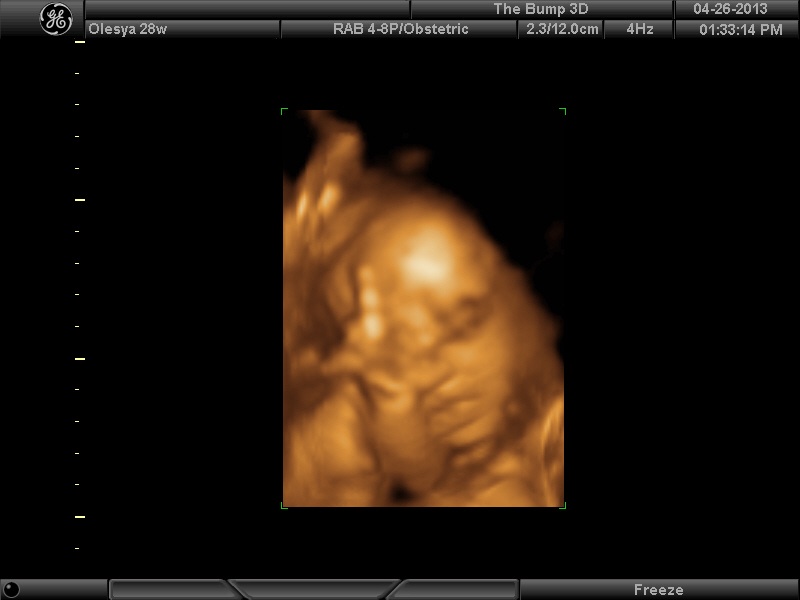

|

Еще одна Джианнка:

| Вложения: |

KENZEL,OLESYA_5.JPG [ 60.02 КБ | Просмотров: 1489 ]